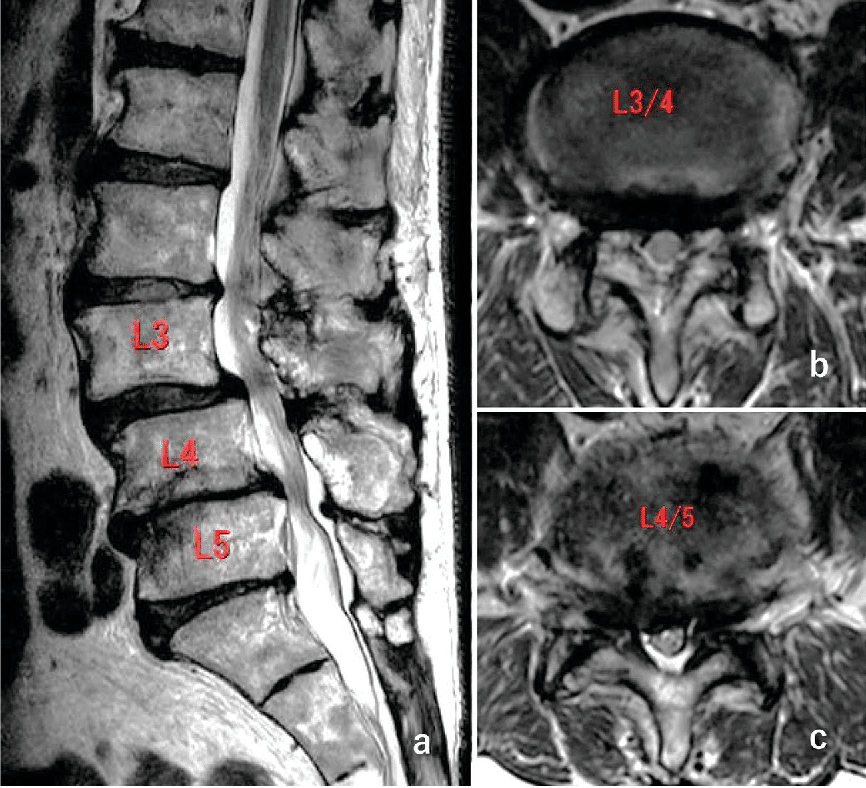

تنگی کانال نخاعی به وضعیتی اطلاق میشود که در آن فضای پیرامون مهرههای ستون فقرات کمتر از حد طبیعی شده و فضای کافی برای عبور نخاع و رشتههای عصبی کاهش مییابد. با باریک شدن این فضا، نخاع یا عصبها ممکن است تحریک یا فشرده شوند و در نهایت فرد دچار کمر درد و حتی درد سیاتیک گردد. معمولاً این اتفاق بهتدریج و طی سالها رخ میدهد.

در بسیاری از موارد، علت اصلی این رخداد، آرتروز یا دیگر تغییرات فرسایشی است که با گذشت زمان و افزایش سن به وجود میآید. از آنجا که فرآیند تنگ شدن کانال نخاعی اغلب کند پیش میرود، ممکن است فرد برای مدتها علامت خاصی نداشته باشد. با توجه به محل تنگی و میزان پیشروی آن، احتمال دارد فرد در ناحیههای گردن، پشت، بازوها، پاها یا حتی دستان خود درد، سوزنسوزن شدن یا احساس ضعف را تجربه کند.

عوامل گوناگونی سبب میشوند که ساختار مهرهها دستخوش تغییر گردد و فضای در دسترس نخاع و عصبهای نخاعی کاسته شود. در این حالت، طناب نخاعی یا عصبها تحت فشار قرار گرفته و منجر به انواع دردهای کمری یا سیاتیک خواهند شد. از دلایل اصلی میتوان به موارد زیر اشاره کرد:

- رشد اضافی استخوان یا پدید آمدن زائدههای استخوانی: وقتی غضروف مفاصل (از جمله مفاصل ستون فقرات) تحلیل میرود، سطح استخوانها روی هم ساییده شده و بدن برای جبران این آسیب، استخوان تازه میسازد. به این بیرونزدگیهای استخوانی اضافی، خار یا زائده استخوانی میگویند. اگر این زائدهها وارد فضای کانال نخاعی شوند، ممکن است به عصبهای عبوری فشار بیاورند. همچنین بیماریهایی مانند پاژه استخوان میتوانند زمینهساز رشد بیش از اندازه استخوان در ستون فقرات شده و به اعصاب آسیب بزنند.

- برجسته شدن یا فتق دیسک: میان مهرههای ستون فقرات، ساختاری دیسکمانند و ضربهگیر قرار دارد که با گذشت زمان خشکتر و نازکتر میشود. اگر جداره خارجی دیسک دچار پارگی یا ترک شود، بخش ژلهای درونی آن بیرون میزند و میتواند موجب فشار به عصبهای اطراف گردد.